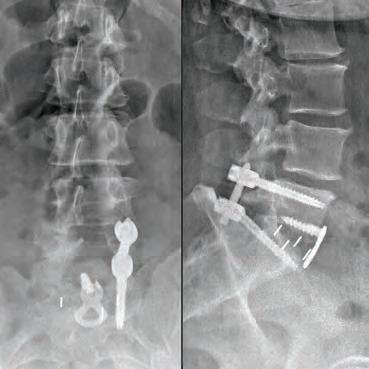

Our cover story this month features Dr. Stephen P. Courtney, a distinguished orthopedic spine surgeon whose commitment to his patients sets him apart in the medical community. Dr. Courtney’s career began humbly, working as an orderly in his teenage years, which sparked his passion for medicine. His academic and professional journey is nothing short of inspiring, having developed innovative spinal care technologies now patented under his name. Dr. Courtney applies a unique blend of hightech and high-touch approaches at Advanced Spine Center, ensuring that every patient receives the personalized care they deserve. Beyond his professional realm, Dr. Courtney is also an avid triathlete, illustrating the deep connection between physical endurance and personal health. Check out his story on page 8.

BOARD-CERTIFIED, FELLOWSHIP-TRAINED ORTHOPEDIC SPINE SURGEON PRACTICING FOR OVER 28 YEARS.

Ths realization inspired Dr. Courtney to design, develop, biomechanically test, complete FDA testing and oversee quality control and validation on a host of tools he created. To date, Dr. Courtney has developed nine spinal product lines and obtained nine patents and 14 trademarks on spine related products.

SURGERY: L5/S1 360° LUMBAR FUSION

SURGERY: L4/5, L5/S1 360° LUMBAR FUSION